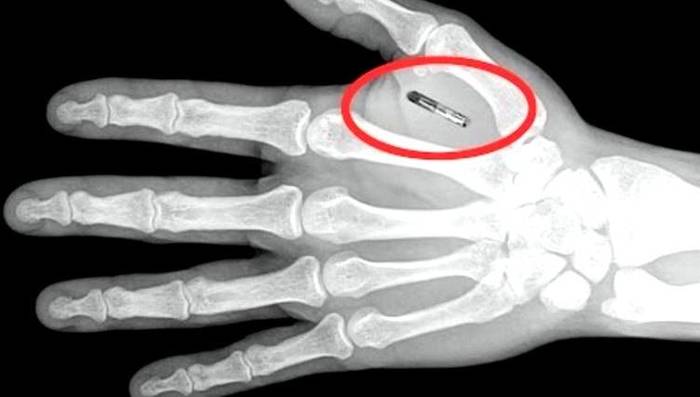

Чипизация населения

Интересная ситуация: чем дальше раскручивается истерика с коронавирусом, тем больше всплывает заинтересованных в ней. Поэтому я просто приведу новость, а выводы делайте сами.

► Если получит одобрение Управления по санитарному надзору за качеством пищевых продуктов и медикаментов США (FDA) в следующем году, двухкомпонентный, встраиваемый в организм датчик поможет обнаруживать новые инфекции за несколько недель до проявления симптомов заболевания.

Пандемии трудно остановить, потому что болезнь распространяется быстрее, чем люди могут быть проверены на нее. Поэтому Пентагон благородно помогает финансировать прорывное исследование для заблаговременного обнаружения гриппоподобных инфекций до проявления их симптомов с помощью внедренного под кожу биосенсора. Компания-разработчик Profusa заявляет, что датчик практически готов и находится на пути к получению разрешения от FDA в начале следующего года.

Датчик состоит из двух частей. Первой является 3-мм нить гидрогеля, вводимая под кожу с помощью шприца. Нить содержит специально сконструированную молекулу, которая меняет цвет, когда организм начинает бороться с инфекцией. Вторая часть - сенсор, крепящийся на кожу снаружи. Он сканирует нить и генерирует сигнал, при изменении ее цвета.

Новое исследование Profusa, о котором компания объявила во вторник, проверит, насколько хорошо датчик сможет обнаруживать инфицирование гриппом за 3 недели до того, как это можно будет определить современными методами диагностики. Поскольку гель не излучает никакого сигнала, он не выдаст позицию солдата, что важно для военных, заявил генеральный директор Profusa Бен Хван.

Бен рассказал, что Profusa получает гранты от Агентства перспективных исследовательских проектов обороны (DARPA) примерно с 2011 года.

Хван добавил, что DARPA помогает компании наладить контакты с подразделениями Пентагона, которые помогут внедрению устройства в военнослужащих, например, с Командованием специальных операций США или с Индо-Тихоокеанским командованием. При этом Хван отказался прокомментировать ход переговоров с военными.